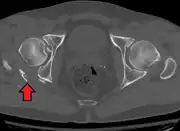

Posterior wallThis is the most common variety of acetabular fracture. It typically occurs due to dashboard injury; when a person travelling in a vehicle involved in a head-on collision, the force applied over the flexed knee travels along the femur bone to the head of the femur, breaking the posterior wall of the acetabulum. The head of the femur is dislocated outside the joint. T shapeWhen a transverse fracture also had a vertical fracture line, it is called a T shape fracture. Here the innominate bone is broken in such a way that all three parts of it, the ilium, the ischium and the pubis are separated from one another. This is a three part fracture. Though both columns are broken, the weight bearing dome is still attached to the main part of the ilium and hence it is not a true fracture of both columns.

Posterior columnAs with posterior wall injury, this also typically occurs due to dash board injury. Posterior column + Posterior wallThese fractures are extensions of elementary fractures. With the involvement of the posterior wall, the difficulty in treatment increases. These fractures are rarely amenable to non-surgical treatment. Due to posterior wall fracture, the hip is usually dislocated posteriorly, requiring immediate reduction of dislocation and surgical reconstruction after a few days.

The posterior column with posterior wall fracture occurs due to dashboard injury. The anteroposterior view may give clues to these injuries. Judet views and CT scans help in knowing the extent of the injury.

• Posterior wall fracture: Iliac oblique and obturator oblique views

• Posterior column fracture: Iliac oblique and obturator oblique views